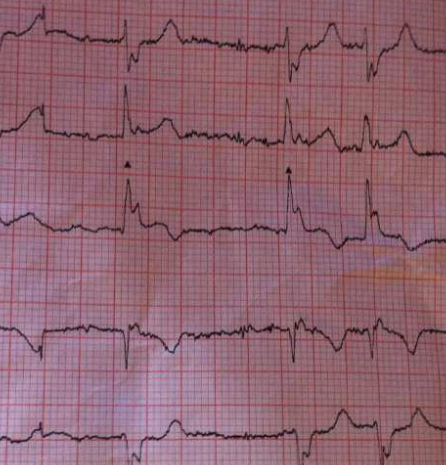

Vous le savez certainement, le canton de Fribourg est précurseur en terme de "premiers répondants" équipés d'AED permettant de prodiguer le plus précocement possible, les premiers soins aux victimes d'arrêts cardio-resp…